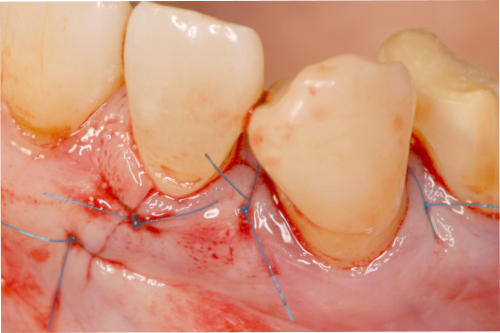

Mikrochirurgischer Wundverschluss